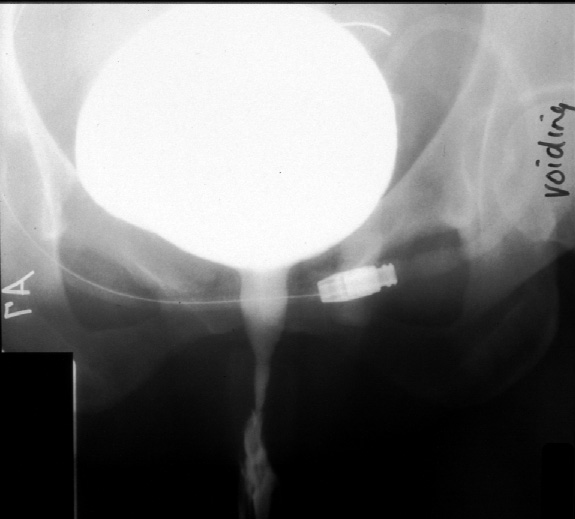

Radiology of Abdomen, Pelvis, and Perineum -- Normal Voiding Cystourethrogram

(Female)

Note. Frontal projectrion taken during urination.

Identify -- bladder, urethra